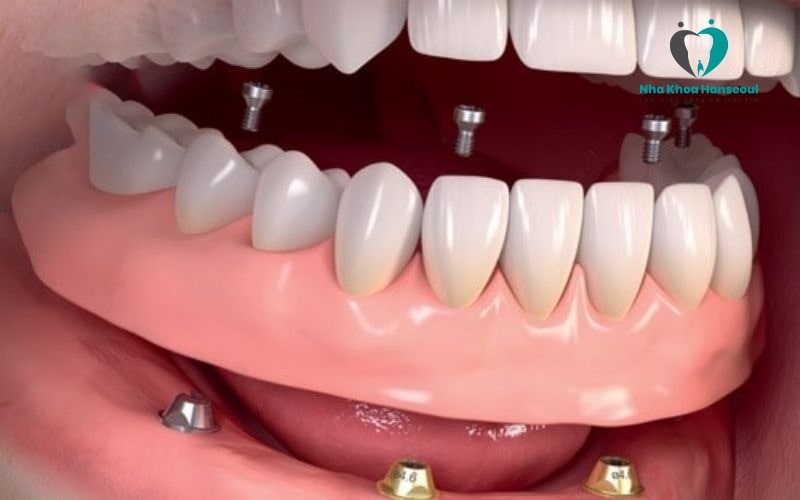

2.4 Implant All On 6

Implant All On 6 là giải pháp cải tiến hơn all on 4 khi sử dụng 6 trụ Implant để đặt vào xương hàm bệnh nhân. Với kỹ thuật All On 6, các trụ chân răng thường được dựng thẳng đứng. Vị trí lắp đặt cũng được phân bố đều khắp cả hàm.

Kỹ thuật này được sử dụng khi xương hàm của bệnh nhân mỏng hơn hoặc không đủ chắc chắn để sử dụng phương pháp implant all on 4.

Đây là 2 kiểu số lượng trụ chân răng phổ biến nhất. Ngoài ra còn có thêm các kiểu dùng 5 hoặc 8 trụ Titanium để phục hình.Tuy nhiên những phương pháp này ít được dùng hơn và chỉ sử dụng trong vài trường hợp nhất định.